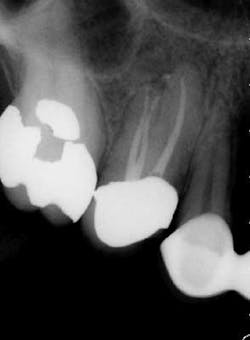

maxillary central incisor with a necrotic pulp. A prominent lateral canal can be seen,

but there is no way to know if multiple microscopic branches are present at any level

of the root canal system.